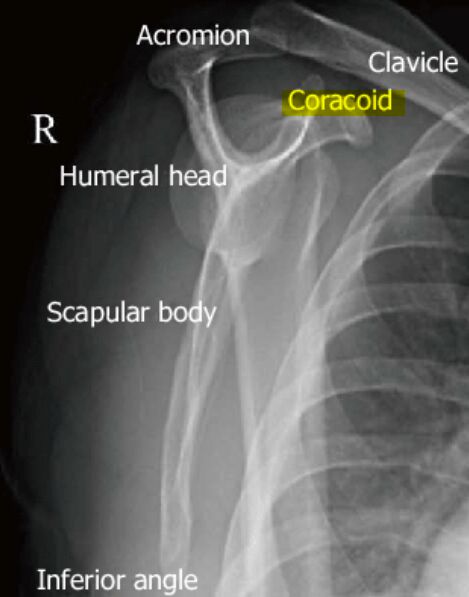

「"Y"的靠前胸上分支解剖構造」就是圖中的coracoid process,coracoid process在身體前側、acromion在身體後側。

圖片來源:https://www.britannica.com/science/acromion

- Acromion(肩峰):標示在編號 8 附近,位於肩部外側並與鎖骨相連,形成肩鎖關節(acromioclavicular joint)。在“Y”形投影中,肩峰構成“Y”的上外側分支。

- Coracoid process(喙突):標示在編號 10 附近,位於肩關節的前上方,向前突出,構成“Y”的上內側分支。

- Scapular body(肩胛骨體):標示在編號 7 附近,構成肩胛骨的大片骨面,形成“Y”形的垂直部分。